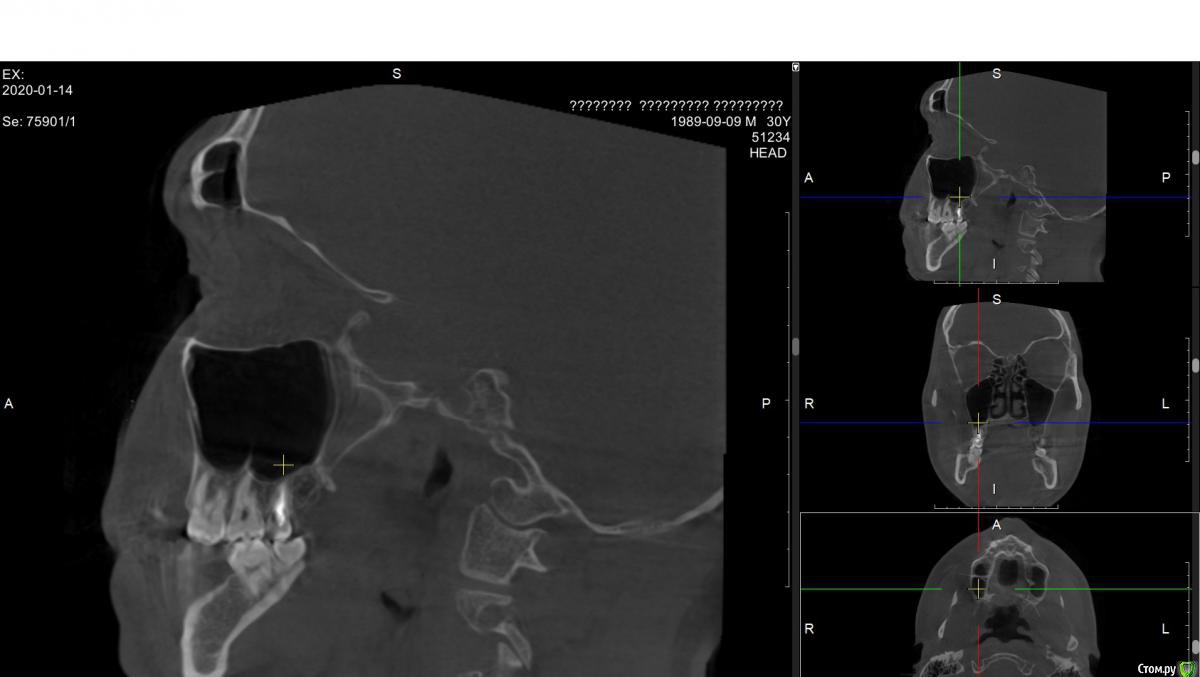

alex889 Опубликовано 8 февраля, 2020 Поделиться Опубликовано 8 февраля, 2020 Подскажите, над предпоследним зубом сверху это инородное тело в гайморовой пазухе? Это могло попасть при лечении каналов зуба мудрости? Может ли такое инородное тело вызывать боли и воспаление в челюстно-лицевой области?Файл КТ: http://fayloobmennik.cloud/7384939 Ссылка на комментарий

alex889 Опубликовано 8 февраля, 2020 Автор Поделиться Опубликовано 8 февраля, 2020 Опешите пожалуйста ваши боли , что именно беспокоит , как давно , что может усиливать боли , а что уменьшать и чем вы их купируете ( обезболиваете)?Последний год периодически возникают боли в районе верхних челюстей или переносицы. Сопровождаются слабостью и головной болью в районе лба. Боли периодически пропадают и снова обостряются с интевалом в пару недель. Боль не слишком сильная, поэтому обезболивающие не использую. Примерно тогда же, год назад, было сложное лечение зуба мудрости и я подумал, что это может быть связано. Ссылка на комментарий

wladdX Опубликовано 10 февраля, 2020 Поделиться Опубликовано 10 февраля, 2020 (изменено) Инородных тел не нашёл. То что Вы приняли за инородное тело - перегородка в пазухе Изменено 10 февраля, 2020 пользователем wladdX 1 Ссылка на комментарий